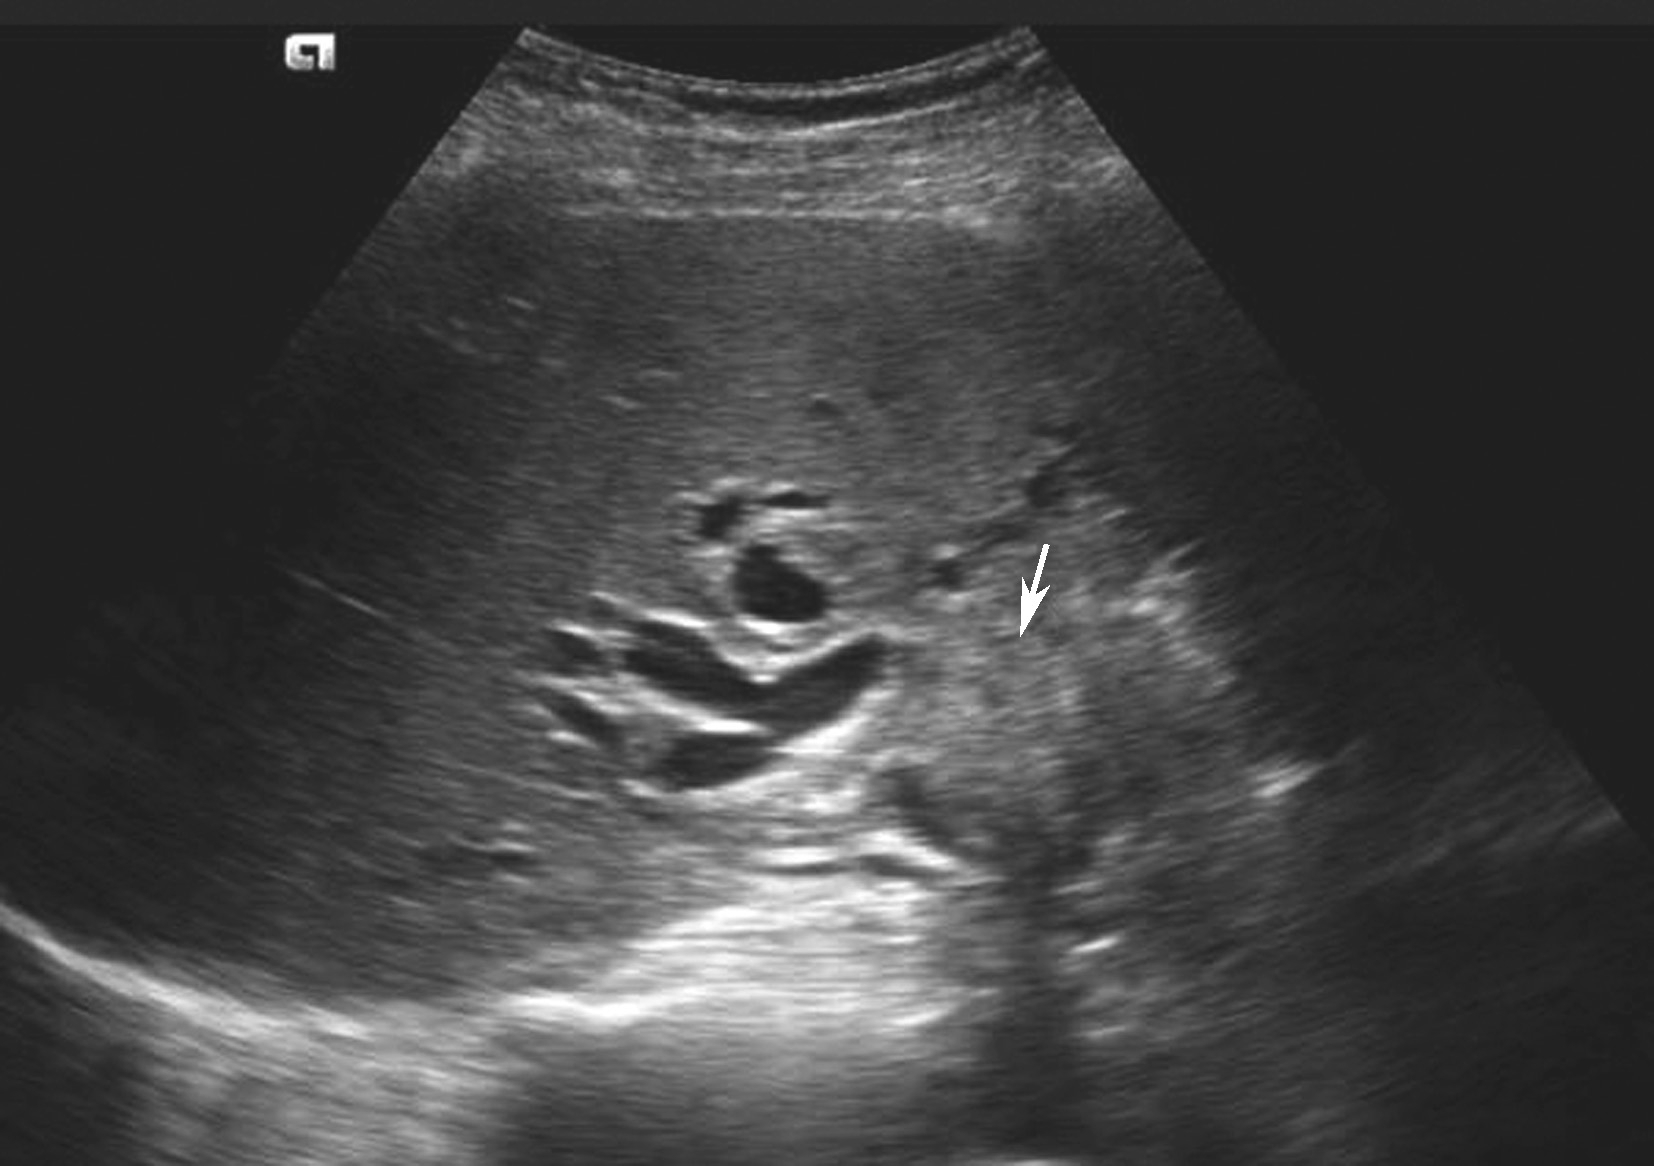

门静脉海绵样变性是指门静脉主干或分支完全、部分栓塞,而后由其侧支静脉形成或管腔的再通所致。引起门静脉阻塞的常见原因是癌栓,其次是血栓。门静脉右支发生率高。临床上主要表现为门静脉高压症状,如脾大、腹水甚至胃肠道静脉曲张性出血。

【声像图表现】

(1)灰阶超声:

肝门区结构紊乱,肝外门静脉周围或管腔内可见多条弯曲成团的血管,呈蜂窝状或网格状无回声区结构,在结构紊乱的肝门部仔细辨认可见管腔狭窄、壁增厚回声增强的门静脉管道,管腔内可见癌栓或血栓,部分可压迫胆道系统造成肝内外胆管扩张。可出现继发门静脉高压声像图改变,如脾肿大、脾静脉及肠系膜上静脉增宽,严重者可见腹水。

(2)彩色多普勒血流显像:

在肝门区蜂窝状或网格状无回声区结构内充满色彩暗淡的彩色血流信号;门静脉狭窄者于门静脉内探及少许连续性彩色血流通过,其周围蜂窝状液性无回声区呈红、蓝相间的不连续彩色血流信号;完全闭塞或栓子充填的门静脉内则无彩色血流信号显示;如图5-21-26所示。

(3)频谱多普勒表现:

门静脉海绵样变性区域于蜂窝状或迂曲的管状无回声区内均可探及门静脉样连续状低速血流频谱;如图5-21-27所示。

图5-21-26 门静脉海绵样变性二维灰阶图像

图5-21-27 门静脉海绵样变性彩色多普勒图像